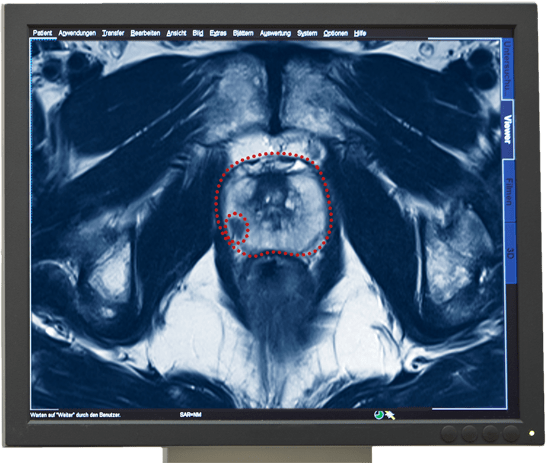

- Prostata mit Krebsherd

Het multiparmetrisch MRI-onderzoek van de Prostaat geldt als het zekerste beeldmateriaal om prostaatkanker te diagnosticeren. Met dit onderzoek kan een kankergezwel gevonden worden en de eigenschappen daarvan vastgesteld en beoordeeld worden.

De informatie over de kwaadaardigheid van een tumor wordt geleverd door een weefselanalyse. Daarvoor worden weefselbiopten uit het verdachte kankergezwel genomen. Met onze Prostaatbiopsie kunnen wij door MRI-sturing gerichte biopten uit het gezwel nemen, pathologisch onderzoeken en de Gleason-score bepalen.

Een multiparametrisch MRI-onderzoek van de prostaat kan de volgende informatie geven, die voor de aansluitende therapie behulpzaam kan zijn.

- Diagnose van de kwaadaardige tumor

- Plaats van de tumor

- Bepaling van de grote en volume van een tumor

- Expansie van de tumor

- Eventuele aantasting van de omliggende structuren of organen

- Eventuele aantasting van de lymfeknopen in het bekken

- Eventuele aanwezigheid van uitzaaiingen in de bekkenbeenderen